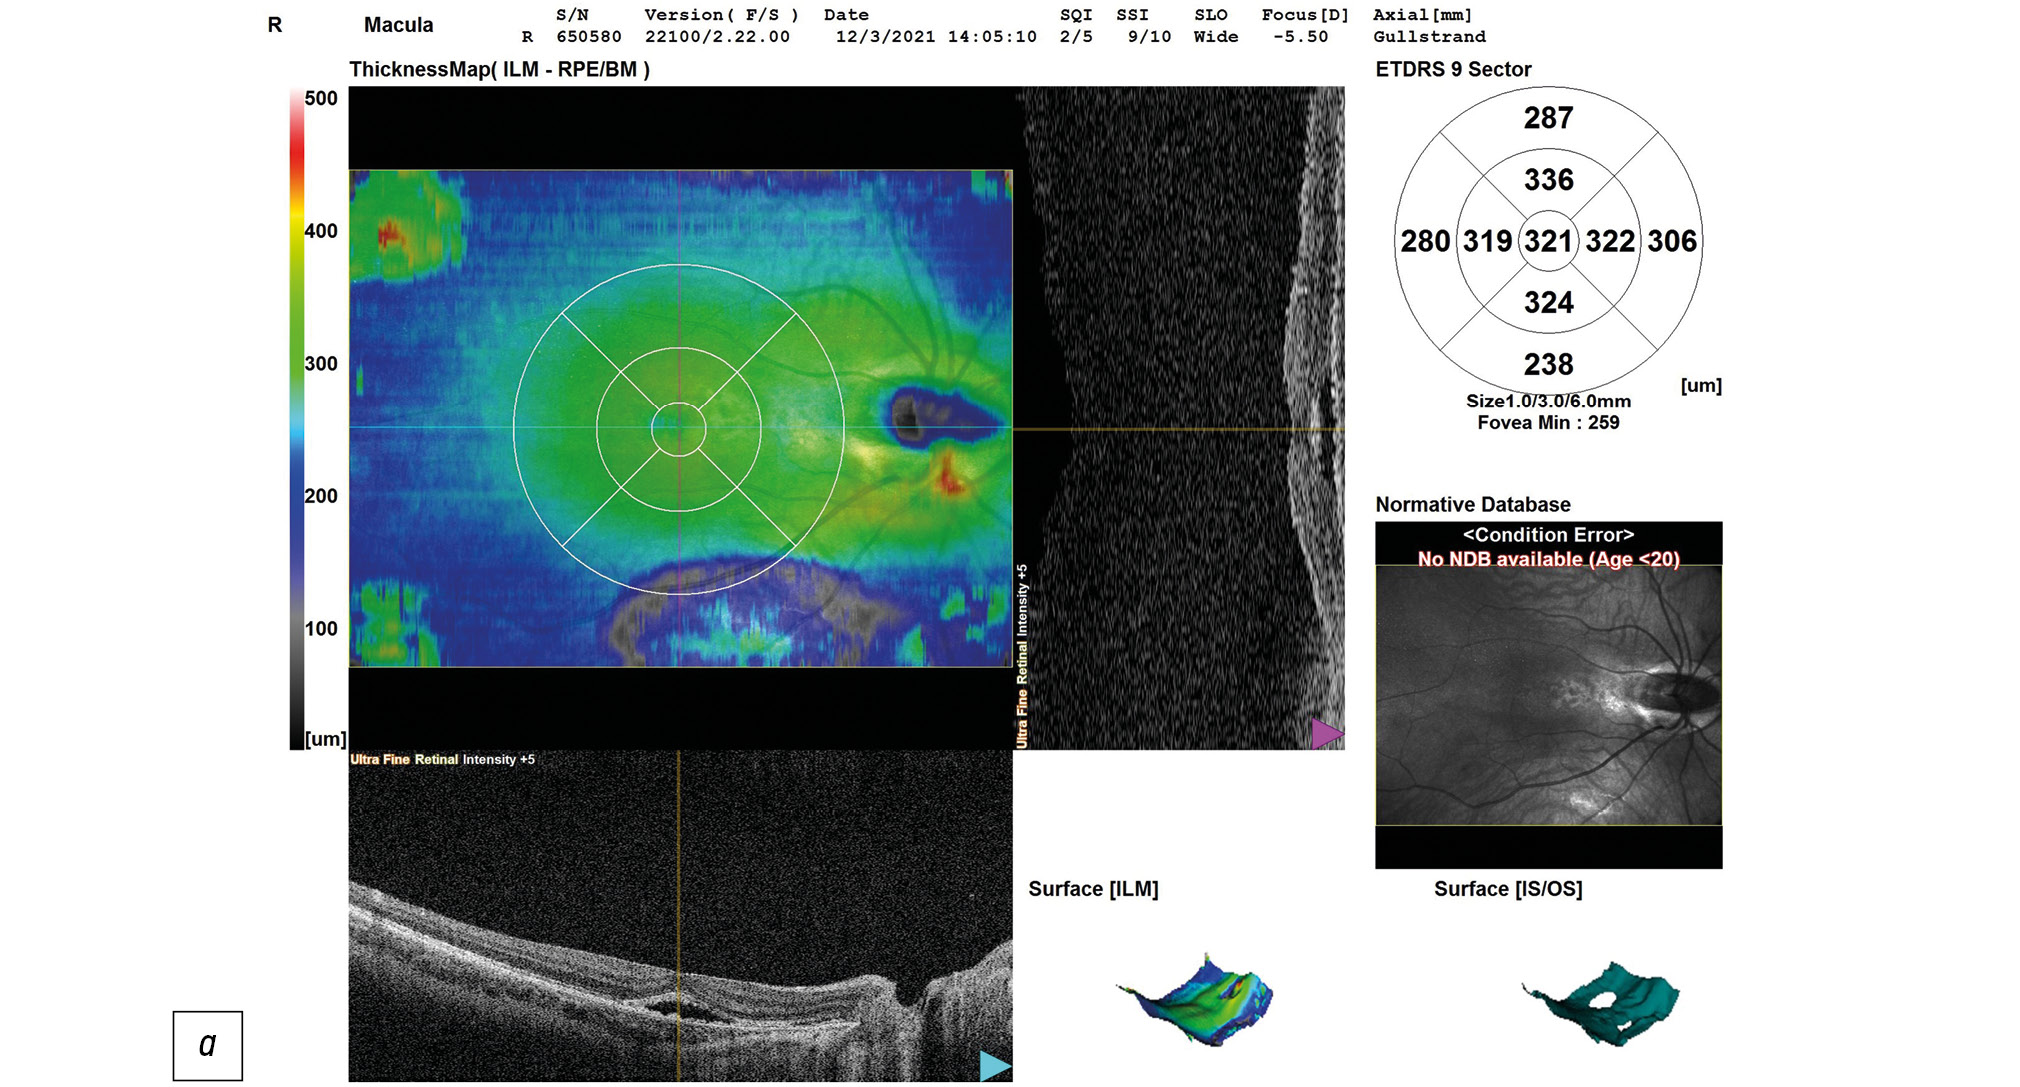

Данные ОКТ макулярной зоны сетчатки правого и левого глаз ребёнка представлены на рисунке 2. Данные ОКТ диска зрительного нерва (ДЗН) правого и левого глаз ребёнка представлены на рисунке 3.

Рис. 2, а. ОКТ сетчатки правого глаза ребёнка на момент поступления в стационар: контур фовеолярной депрессии сглажен, отслойка нейроэпителия в макулярной зоне, деструкция и дезорганизация нейроэпителия и слоя пигментного эпителия, центральная толщина сетчатки 321 мкм.

Справа — контур фовеолярной депрессии сглажен, отслойка нейроэпителия в макулярной зоне, деструкция и дезорганизация нейроэпителия и пигментного эпителия, центральная толщина сетчатки (ЦТС) 321 мкм, Слева — структура сетчатки в макуле не изменена, ЦТС 276 мкм. Справа экскавация ДЗН деформирована, расширена, заполнена субстратом однородной рефлективности средней степени, перипапиллярная щелевидная отслойка нейроэпителия в верхне-височном (рис. 3а) и нижне-височном (рис. 3б) квадрантах. Слева — экскавация ДЗН деформирована, расширена.